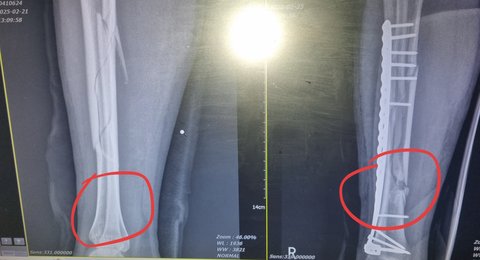

저는 올해 초, 50cm 높이에서 발을 헛디뎌 정강이뼈(경골·비골) 골절로포항의 한 병원 응급실에 갔습니다.엑스레이와 CT 검사를 마친 뒤 담당 의사는 “수술이 필요하다”는 소견을 주었습니다.수술 방법을 물었지만, 의사는“뼈 고정 방식에는 여러 가지 방법이 있습니다. 비의료인에게 설명해봤자 몰라요. 그냥 믿고 맡기세요.”라고 하였습니다.저와 어머니는 그 말을 믿었습니다.그러나 수술 중 예상치 못한 문제가 발생했습니다.

의사는 무릎 쪽으로 금속정을 삽입해 뼈를 고정하려 했으나,삽입 과정에서 경골이 으스러졌습니다.그는 금속정을 제거하고, 뼈 옆에 금속판을 대고 나사로 고정하는 방식으로 수술 방법을 변경했습니다.만약 수술이 정상적으로 끝났다면 저는 문제 삼지 않았을 것입니다.하지만 이후 상황은 그렇지 않았습니다.

감염은 결국 뼈로 번져 골수염(osteomyelitis) 으로 악화되었습니다.그런데도 의사는 대학병원 진료를 받는 날까지“뼈는 멀쩡하다. 항생제를 쓰면서 좀 더 지켜보자.”라며 골수염을 방치했습니다.대학병원에 가서 수술해보니 뼈는 이미 괴사되어 죽어있었습니다.결국 뼈 14cm를 절제하고 이식 수술을 받아야 했습니다.올해만 7번의 수술을 받았고,지금도 만성 골수염으로 평생 항생제 치료를 받아야 합니다.